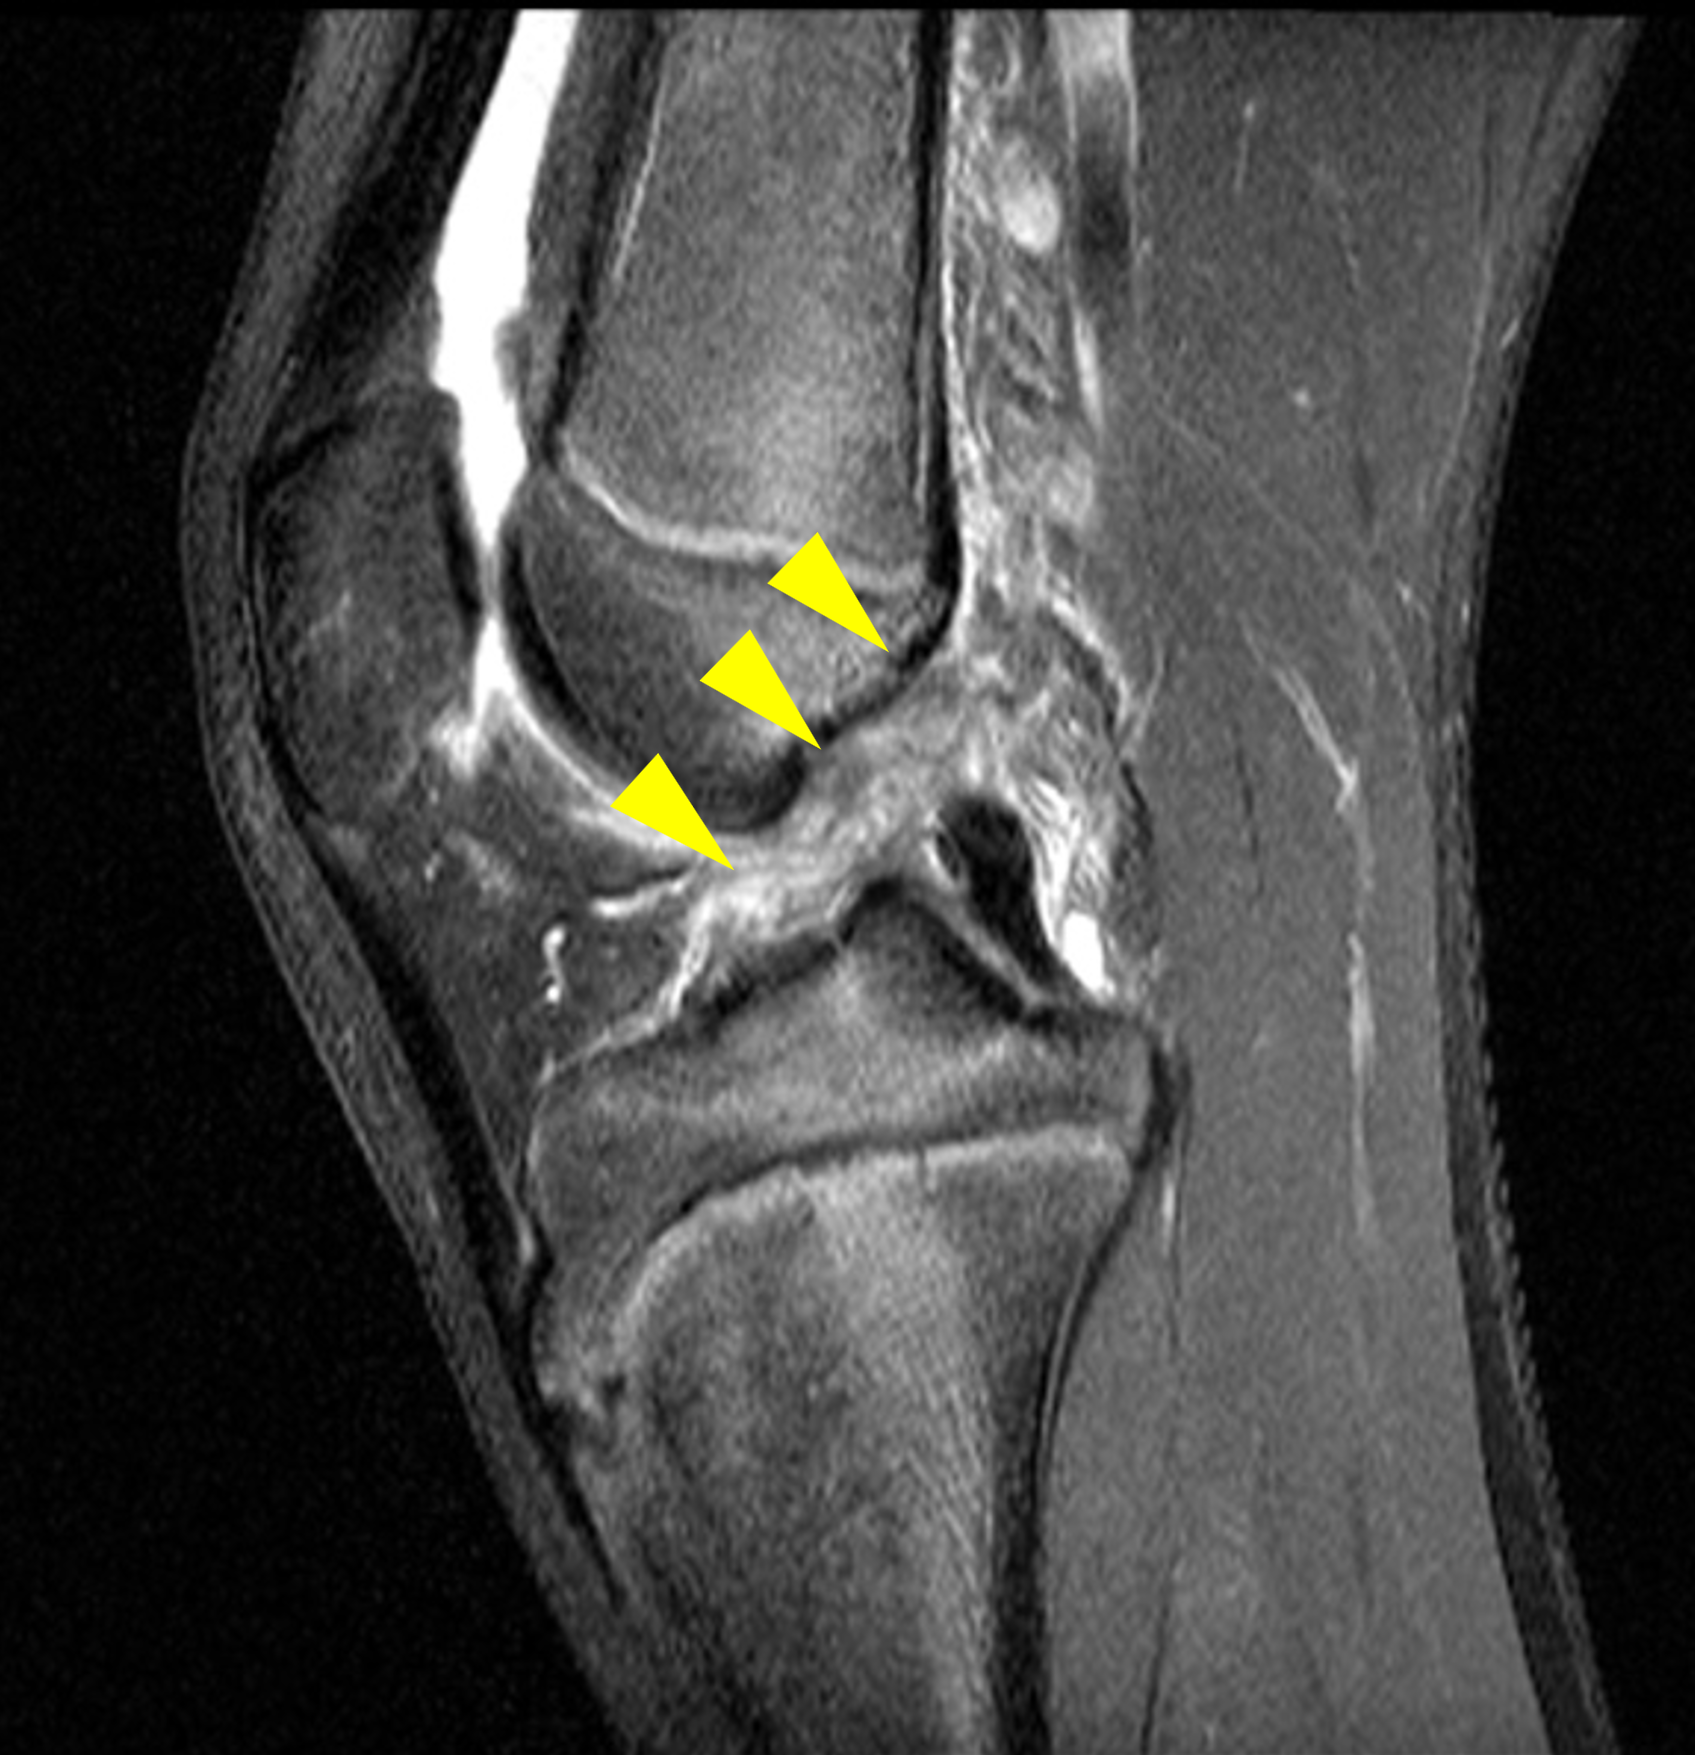

A 19-year-old collegiate baseball player sustained a twisting injury to the knee 3 weeks earlier. Sagittal (1A) proton density-weighted fat-suppressed image through the intercondylar notch, (1B and 1C) proton density-weighted images through the medial compartment, and (1D) fat-suppressed proton density image through the medial compartment are provided. What are the findings? What is your diagnosis?

Figure 2: (2A) Sagittal image through the intercondylar notch shows a complete tear of the anterior cruciate ligament (arrowheads). (2B and 2C) Near the posterior meniscocapsular junction of the medial meniscus, there is disruption of the posterior meniscotibial ligament (red arrow) and irregularity of the posterior meniscocapsular ligament (yellow arrow). (2D) On the fluid-sensitive sequence, linear high signal intensity is interposed between the ligaments and the posterior horn of the medial meniscus (arrowheads).

Anterior cruciate ligament tear with a medial meniscal ramp lesion.